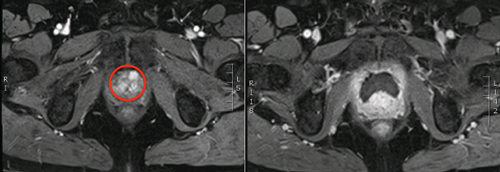

Figure 2: Left - red circle highlighting posterior tumour, Right -

post HIFU dynamic contrast enhanced MRI showing ablated area.

Focal therapy developed from the index lesion theory of prostate cancer. In essence, the largest and highest grade lesion within the prostate almost always drives the natural history of the disease (Figure 1 and 2). The technological evolution and innovation needed to facilitate focal therapy was firstly, the ability to accurately detect, localise and characterise areas of significant cancer (often the index lesion); and secondly, the ability to selectively ablate prostate tissue. In this article, we summarise the results of these advancements, along with the latest clinical data and build the argument that FT is ready for prime time.